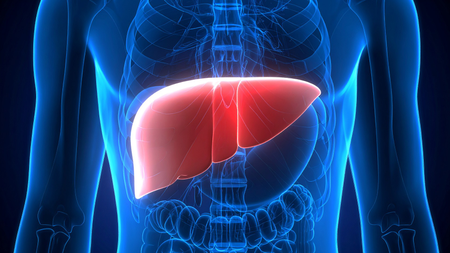

New Delhi, June 14 (IANS) Alcohol-related liver disease deaths are increasing rapidly among women and young adults, according to new research.

One reason women may be affected more is because of how the body processes alcohol.

Biologically, women are less able to break down alcohol than men. That means even a little drinking can have a bigger impact on their organs over time, the researchers explained.